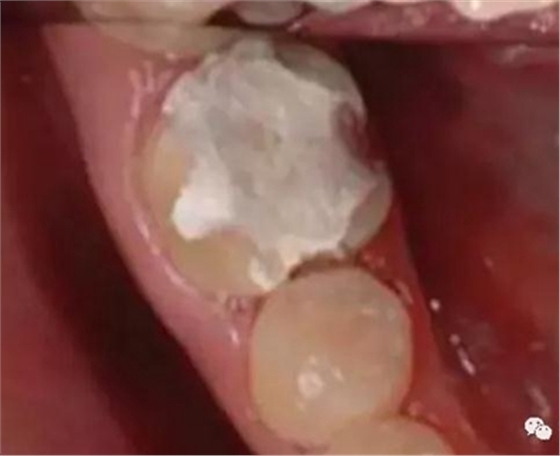

增加牙體抗力形的措施

3.基牙具有良好的抗力形